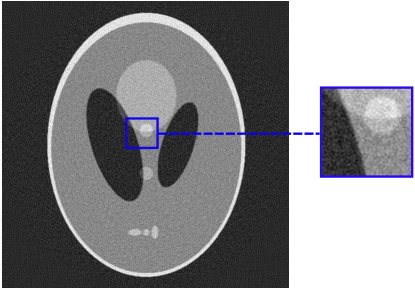

5 Benchmark procedure

To assess the performance of the HLSF, four phantoms with structural patterns of different complexity have been considered (Fig. 4). PH-1 in Fig. 4(a) is the segmentation of a reconstructed slice of mouse lung tissue at micrometer scale. PH-2 in Fig. 4(b) is a multilevel segmentation of a MRI scan of a human brain. PH-3 in Fig. 4(c) is a multilevel segmentation of a CT slice of a human lung. PH-4 is the well-known Shepp-Logan phantom [16].

Refer to caption

(c) PH-3

Figure 4: Set of simulated data used to benchmark the HLSF. PH-1 has 784 ×\times 784 pixels; PH-2 has 592 ×\times 592 pixels; PH-3 has 500 ×\times 500 pixels; PH-4 has 512 ×\times 512 pixels.

Figure 9: Reconstructions performed by FBP and CFBP with Hanning filter of a PH-3 sinogram 108 views ×\times 500 pixels (SF = 14%) + Poisson noise with σ=2.2%𝜎percent2.2\sigma=2.2\% of the original sinogram mean value.